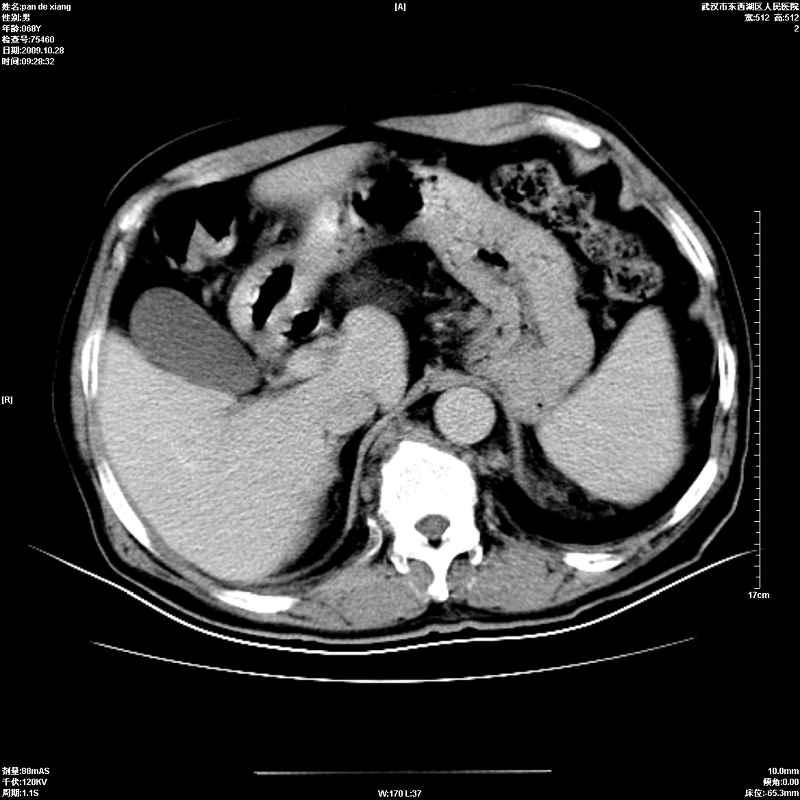

以下是引用杀毒软件在2009-10-28 20:41:00的发言:[br]结合临床考虑---白血病双肾改变或淋巴瘤。

以下是引用zxl51642在2009-10-29 9:59:00的发言:[br]结合临床“单克隆免疫球蛋白血症”,考虑双肾为继发损害并肾功能不全(尿中大量igg及少量iga、igm等大分子免疫球蛋白滤出所致继发损害),椎前软组织肿块为髓外造血。与浆细胞瘤有区别,平扫时有战友说的很清楚。